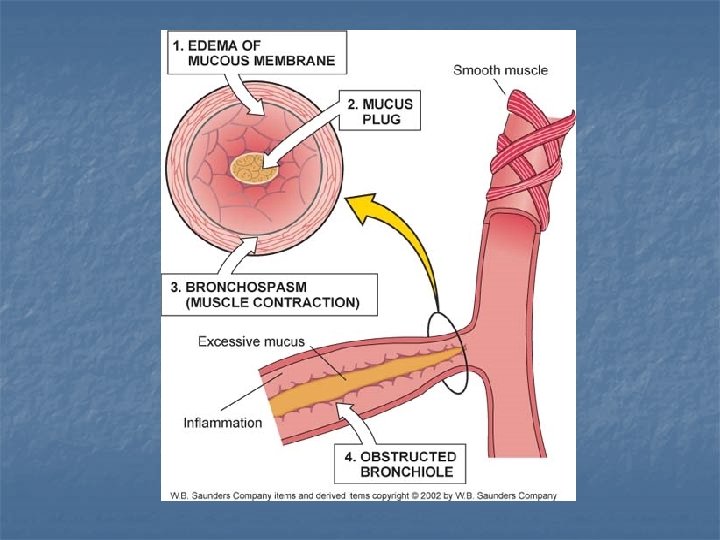

ASTHMA n n Asthma is a chronic respiratory disorder Bronchi and bronchioles are affected – bronchiole muscles tighten, mucus is produced – breathing is difficult

ASTHMA - causes n n Generally it is thought that asthma is somewhat inherited TRIGGERS – include pollen, dust, smoke, pets, exercise

ASTHMA - symptoms n n Chest tightness Wheezing Night-time cough Restricted breathing